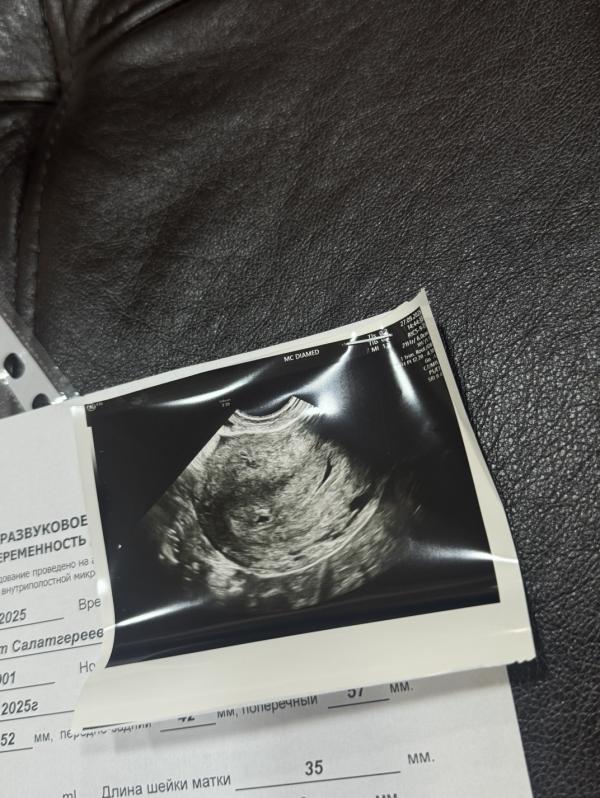

Нашли мою креветку

Срок по узи соответствует 4недели 6 дней

По месячным 5,2

Отстает на несколько дней